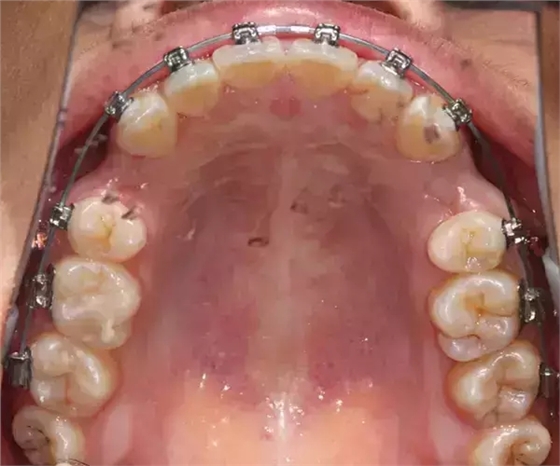

患者側(cè)面凸,鼻唇角較銳,笑時(shí)露齦笑明顯上下牙列擁擠,磨牙尖牙Ⅱ 類關(guān)系,3 度的深覆牙合,上頜中切牙伸長(zhǎng)內(nèi)傾拔除上頜雙側(cè)的第一前磨牙,先粘上頜高轉(zhuǎn)矩的自鎖托槽排齊牙列,唇向開(kāi)展上頜切牙,有一定的覆蓋,粘下頜標(biāo)準(zhǔn)轉(zhuǎn)矩托槽,上頜 1, 2 之間植入種植支抗壓入,同時(shí)后牙 5, 6 之間植入種植支抗內(nèi)收前牙,打開(kāi)咬合關(guān)閉間隙。治療關(guān)鍵:前牙轉(zhuǎn)矩的控制第 1 個(gè)月 上頜粘上 Damon Q 高轉(zhuǎn)矩托槽,上 .014 熱激活 NiTi 絲。第 3 個(gè)月 上換 .014 x .025 熱激活 NiTi 絲。第 5 個(gè)月 上頜基本排齊,覆蓋增大,上換 .017 x .025 NiTi絲,下頜粘托槽,下 .014 熱激活 NiTi 絲。第 7 個(gè)月 上 .017 x .025 NiTi 絲加搖椅,下?lián)Q .014 x .025 熱激活 NiTi 絲第 9 個(gè)月 上頜換 .019 x .025 NiTi 絲加搖椅,下頜換 .017 x .025 NiTi 絲第 11 個(gè)月 下頜換 .019 x .025 加搖椅,上頜 1, 2 之間, 5, 6 之間植入種植釘,下頜出現(xiàn)散隙。第 13 個(gè)月 上頜換 .019 x .025ss 加搖椅,前牙種植釘用 Power Chain 壓低前牙(每側(cè) 100g),后牙種植釘關(guān)閉間隙(每側(cè) 150g),下?lián)Q .019 x .025ss,Power Chain 關(guān)閉間隙。第 19 個(gè)月 上頜前牙基本壓低到位去除前牙種植釘,繼續(xù)用關(guān)閉間隙,下頜散隙關(guān)閉。

第 22 個(gè)月 上頜覆蓋變小,去除 5, 6 之間種植釘,后牙前移關(guān)閉間隙。第 30 個(gè)月 患者未配合中線牽引,下中線仍有 1mm 右偏,患者對(duì)矯治效果滿意要求拆除,拆除固定矯治器,取模制作壓模保持器。 1.骨性 Ⅱ 類的患者內(nèi)收前牙時(shí)需對(duì)上頜前牙的轉(zhuǎn)矩進(jìn)行較好的控制才能獲得良好的面型和唇部形態(tài)。 2.露齦笑的患者治療前要分析其病因是唇、牙齦、牙齒、牙槽骨、上頜骨或多種因素結(jié)合,再制定矯治方案。 3.Ⅱ 類第二分類伴露齦笑的患者的上頜前牙移動(dòng)軌跡是唇向開(kāi)展-壓低-整體內(nèi)收。 4.Ⅱ 類第二分類牙齒舌傾比較厲害的情況,上頜中切牙慎用樹(shù)脂咬合墊。 5.壓低前牙或控根移動(dòng)時(shí)容易發(fā)生牙根的吸收,需輕力緩慢的移動(dòng)。